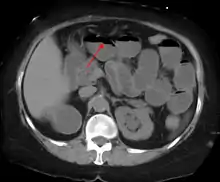

Contrast enema or small bowel series or CT scan can be used to define the level of obstruction, whether the obstruction is partial or complete, and to help define the cause of the obstruction. The appearance of water-soluble contrast in the cecum on an abdominal radiograph within 24 hours of it being given by mouth predicts resolution of an adhesive small bowel obstruction with sensitivity of 97% and specificity of 96%.[18]

Causes of bowel obstruction include adhesions, hernias, volvulus, endometriosis, inflammatory bowel disease, appendicitis, tumors, diverticulitis, ischemic bowel, tuberculosis and intussusception.[1][2] Small bowel obstructions are most often due to adhesions and hernias while large bowel obstructions are most often due to tumors and volvulus.[1][2] The diagnosis may be made on plain X-rays; however, CT scan is more accurate.[1] Ultrasound or MRI may help in the diagnosis of children or pregnant women.[1]